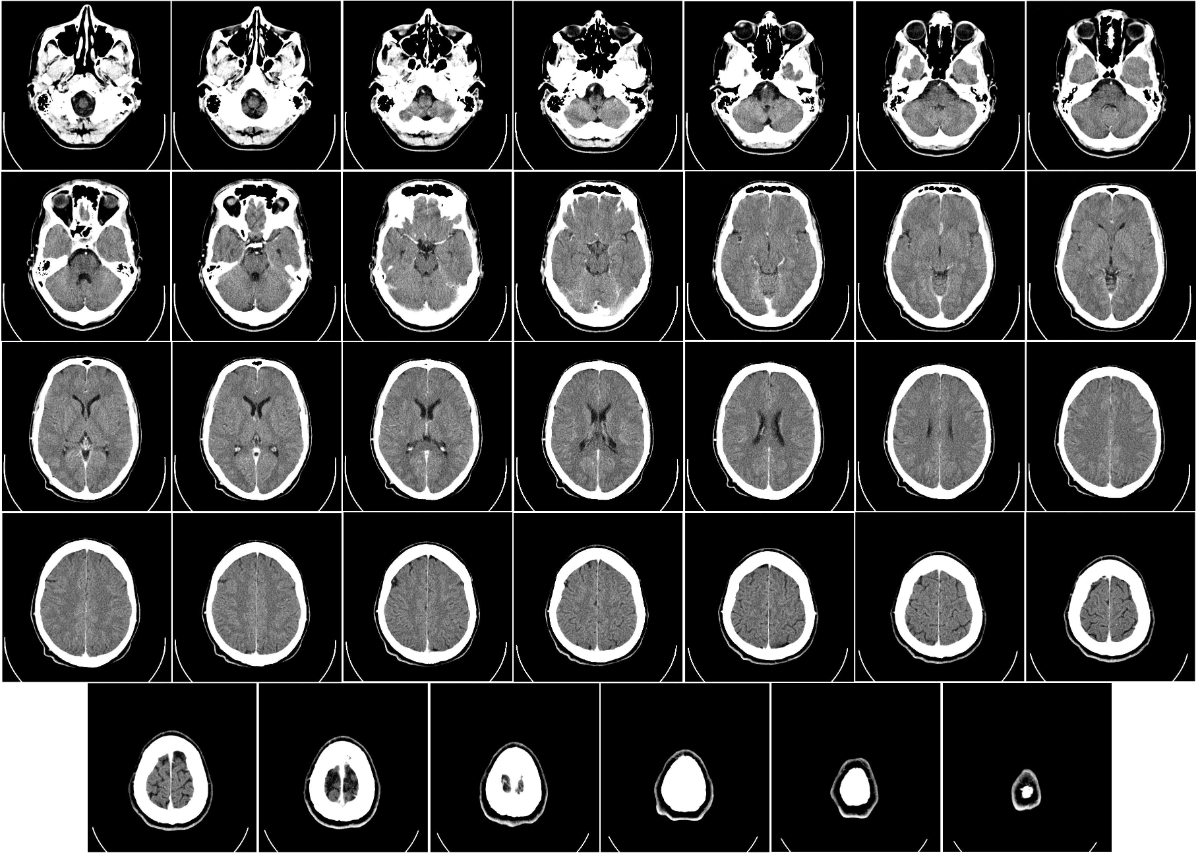

Tomografia komputerowa, TK, CT, tomokomputer (tylko na Pomorzu to słyszałem xD)

Computed_tomography_of_human_brain_-_large.pngKtoś wymyślił obrotowe RTG, i nawet je zrobił. Na zdjęciu przekroje (projekcje poprzeczne) mózgu na różnych wysokościach.

Zasada działania: RTG kręcące spiralę wokół pacjenta. Lampę i matrycę umieszczamy na obręczy, często stosujemy przesłonę, żeby naświetlać wąski wachlarz lub słupek (o tym może kiedyś rozwinę), pacjenta kładziemy na stole i równocześnie kręcimy obręczą i przesuwamy stół. Dostajemy obraz 2D (sinogram), w którym każdy kolejny rząd jest zrobiony pod trochę innym kątem, i obrazuje przekrój ciała o pewnej grubości. Potem stosując różne techniki obliczeniowe rekonstruujemy go do obrazu 3D.

Co widzimy: to samo co w klasycznym RTG, tylko w 3D. Możemy sobie pacjenta wirtualnie "przekroić" w dowolnej płaszczyźnie, możemy zrobić model 3D pokazujący wybrane tkanki na podstawie ich gęstości - oprogramowanie dostarczane razem z TK ma wgrane gotowce, wystarczy poprzesuwać parę suwaczków, żeby np. wyciąć mięśnie i kości, zostawiając same naczynia krwionośne.

Ograniczenia i zagrożenia: promieniowanie, znów, jest go jeszcze więcej niż przy RTG - o szczegółowych planuję też coś napisać. Dodatkowo zdarzają się artefakty - fałszywie widoczne obiekty np. wokół śrub, płytek, rozruszników czy innych metalowych obiektów wewnątrz pacjenta (albo na nim - klucze, obrączka itp.). Wynikają one z przybliżonych obliczeń matematycznych przy rekonstrukcji sinogramu w obraz 3D.